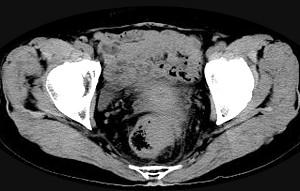

问题 男,56岁,排便形状改变,便不尽感,CT检查如图所示,下列说法正确的是 ( )

选项 A、此为直肠息肉 B、此为直肠癌 C、其表面光滑,边界清楚 D、肠腔未见狭窄 E、肠壁上有蒂状新生物 单选题

答案 B